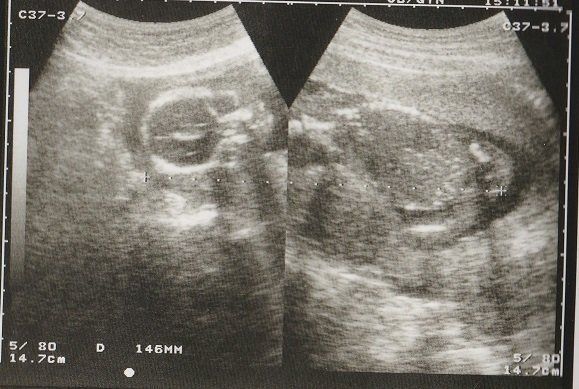

妊娠18週目のエコー写真 画像におさまらないほどに成長する

赤ちゃんがどんどん大きくなり、1枚の超音波画像ではおさまりきらなくなりました。画像を2枚くっつけて赤ちゃんの大きさを測っています。

BPD(児頭大横径=頭の直径)を測って、胎児の発育を調べるようです。ここまで、母子ともに特に異常も無く過ごせました。